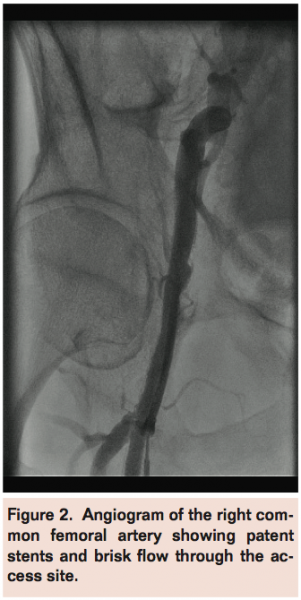

Access was obtained through the existing stent in the right femoral artery using a micro-puncture access kit and upsized to a 7 Fr sheath (Figure 1). After crossing the aortoiliac bifurcation into the left external iliac artery using a Rim catheter (Cordis Corporation), a 7 Fr Ansel sheath (Cook Medical) was advanced over an Amplatz stiff wire (Cook) into the left external iliac artery. Angioplasty was performed on the left SFA with good angiographic result and brisk flow into the left foot.